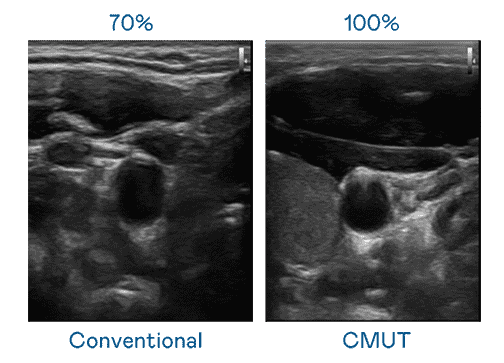

CMUT 技术是一种用电容式微机电元件来产生超音波讯号的技术。。。。与传统 PZT 压电式技术相比,,,,CMUT 频宽增加 30%,,更宽频的超音波讯号让影像解析度大幅提升,,,是实现高影像品质医疗超音波扫描、、促进精准医疗发展的关键技术。。。

大频宽带来超清晰影像

超音波影像的解析度高低,,,首先取决于探头能发出的讯号频宽。。。。巨星国际 CMUT 可提供高清晰的超音波讯号,,,提供高频宽、、、、高灵敏度、、、影像纹理细节更高的超音波影像,,协助医护人员缩短影像判读时间及利用精准的医疗影像进行诊断。。。